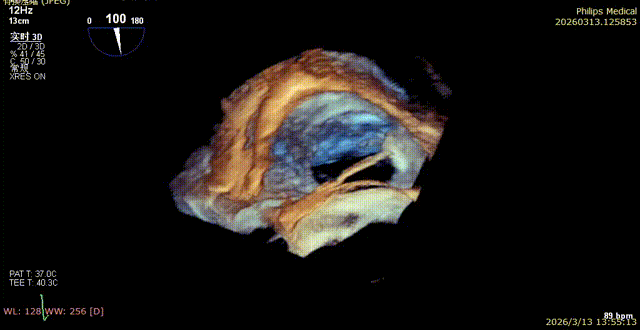

1. The first 14T device was positioned under the mid-esophageal bicaval view on TEE, and the tip of the delivery catheter was observed to point to the posterior-septal commissure of the tricuspid valve using 3D mode.

2. Under 3D mode switched to MPR-MultiVue mode, the trajectory was adjusted to anchor the tricuspid annulus.

3. The pull test was completed under MultiVue mode.

4. After opening the clipping component, the orientation was adjusted under 3D mode.

5. Apposition to the tricuspid annulus under 3D mode.

6. Under the guidance of MultiVue mode and DSA, the anchoring pull rod was retracted and the clipping component was closed to complete the clip application.